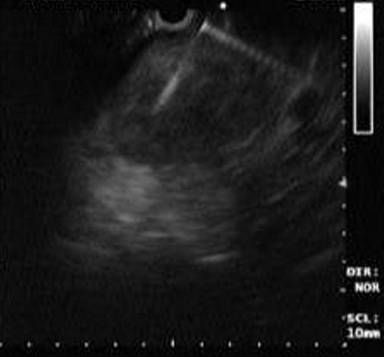

A 27-year-old married woman presented to our facility with abdominal pain and fullness of 20 days duration. She denied alcohol intake and she is a non smoker. There was no history of abdominal trauma or any drug intake for any other illnesses. Our clinical diagnosis was pancreatitis with fluid collection around the pancreas based on the serum amylase and lipase which were 720 U/L (reference range: 23-80 U/L) and 210 U/L (reference range: 0-60 U/L), respectively. CT scan of abdomen revealed huge hypodense lesion in pancreas suggestive of pseudocyst. (Figure 1). Patient also had a small 3x3 cm swelling over the right jaw. We subjected the patient for endoscopic ultrasonography (EUS) which revealed a 6x6 cm cystic lesion involving head and body of pancreas. There was no gallstones visualized. As the EUS showed irregular borders of the cyst we did cyst fluid aspiration for analysis (Figure 2). Cyst fluid amylase, CA 19-9, and CEA were 13,500 U/L, 28 U/mL, and 17 ng/mL, respectively. Cytological examination (fine needle aspiration; FNA) showed large, pleomorphic mononucleated cells having large, hyperchromatic, pleomorphic nuclei and moderate to ample amount of pale or vacuolated cytoplasm and a multinucleated giant cell at the center suggestive of choriocarcinoma (Figure 3). Biopsy of the lesion in left jaw also revealed germ cell tumor. Serum beta human chorionic gonadotropin was 98,000 mg/dL. Interestingly, alpha-fetoprotein was 9.6 ng/mL which excluded other giant cell tumors except choriocarcinoma. Choriocarcinoma is a germ cell tumor which presents with normal alpha-fetoprotein and very high beta human chorionic gonadotropin levels.

Figure 2. Endoscopic ultrasonography guided fine needle aspiration of cystic lesion of pancreas. |